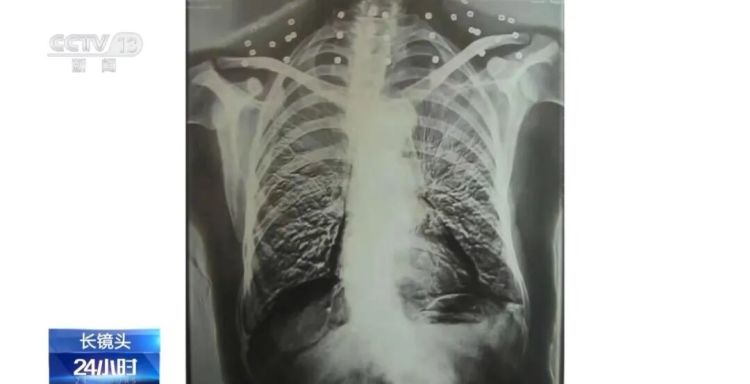

这张图片是82岁吴以先老人的CT照,当初拍片时,医生说,“老先生,您要把项链取下来再做CT。”

吴以先说,“我从来没戴过项链,你看会不会是弹片?”由此,引出了老人一段不平凡的往事。

20年前,吴以先做CT检查时,由于颈部有许多弹片,医生误将弹片认作是他戴的项链,于是提醒他要把项链取下来,再做检查。

实际上,在吴以先的颈部和腹部,共分布着33个弹片。

回到连队后,吴以先开始恢复用右手写字。虽然伤势好转,但是被弹壳打穿的右手落下了残疾。直到现在,吴以先体内的弹片都没有取出,每到天气变化的时候,留有弹片的部位就会有痛感。

但吴以先不考虑取出弹片,他说这是他与战友并肩作战的见证,是他的勋章。

33个弹片组成的“项链”,是一名军人的光荣,也是一位英雄的至诚本色。